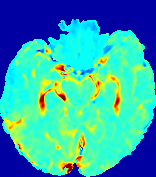

LesionRefer to captionRefer to captionRefer to captionRefer to captionRefer to captionRefer to caption𝐕rgbsubscript𝐕𝑟𝑔𝑏{\bf{V}}_{rgb}Refer to captionRefer to captionRefer to captionRefer to captionRefer to captionRefer to caption𝐕2subscriptnorm𝐕2{\|\bf{V}}\|_{2}Refer to captionRefer to captionRefer to captionRefer to captionRefer to captionRefer to captionRefer to caption3.53.53.52.82.82.82.12.12.11.41.41.40.70.70.70.00.00.0(mm/s)𝑚𝑚𝑠(mm/s)D𝐷DRefer to captionRefer to captionRefer to captionRefer to captionRefer to captionRefer to captionRefer to caption0.0200.0200.0200.0160.0160.0160.0120.0120.0120.0080.0080.0080.0040.0040.0040.0000.0000.000(mm2/s)𝑚superscript𝑚2𝑠(mm^{2}/s)Slice #1Slice #2Slice #3Slice #4Slice #5Slice #6

Figure 4: PIANO feature maps for another patient in the ISLES 2017 training set, where the lesion is located in the right hemisphere. Top row: segmented stroke lesion region (white) on different slices. The corresponding slices for the PIANO feature maps are shown in the following rows.

For a better insight into an estimated velocity field 𝐕𝐕{\bf{V}} and diffusion field 𝐃𝐃{\bf{D}}, we compute the following maps: (1) 𝐕rgbsubscript𝐕𝑟𝑔𝑏{\bf{V}}_{rgb}: Color-coded orientation map of 𝐕=(Vx,Vy,Vz)T𝐕superscriptsuperscript𝑉𝑥superscript𝑉𝑦superscript𝑉𝑧𝑇{\bf{V}}=(V^{x},V^{y},V^{z})^{T}, obtained by normalizing 𝐕𝐕{\bf{V}} to unit length and mapping its 3 components to red, green, blue respectively; (2) 𝐕2subscriptnorm𝐕2\|{\bf{V}}\|_{2}: 222 norm of 𝐕𝐕{\bf{V}}; (3) D𝐷D: scalar field in Eq. 5.

Fig. 3 and Fig. 4 show the PIANO feature maps estimated from two ISLES 2017 patients: all are highly consistent with the lesion in both cases. Details of the blood flow trajectories are revealed in 𝐕rgbsubscript𝐕𝑟𝑔𝑏{\bf{V}}_{rgb} by the ridged patterns and the sharp changes of colors in the unaffected (right) hemisphere, while the flat patterns appearing within the lesion provide little directional information about the velocity and indicate low velocity magnitudes. Velocity magnitudes are more directly visualized via 𝐕2subscriptnorm𝐕2\|{\bf{V}}\|_{2}, from which one can easily locate the lesion where 𝐕2subscriptnorm𝐕2\|{\bf{V}}\|_{2} is low. D𝐷D also indicates lower diffusion values in the lesion, though with less contrast potentially due to the fact that it captures the accumulated effect of CA diffusion at the voxel-level.